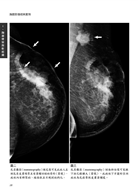

病例2 男性乳癌(Male breast cancer) 9